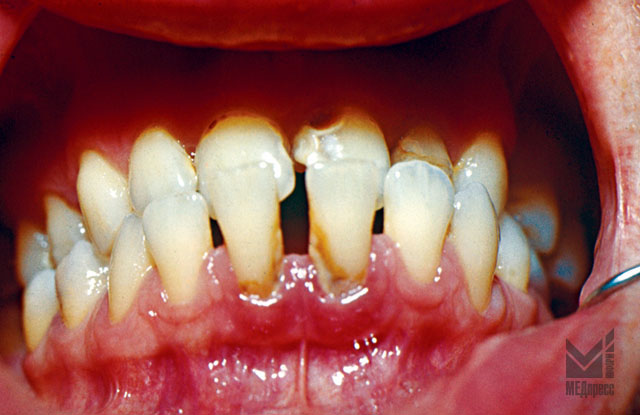

Рис. 5.Антериальный прикус. Гиперемия и отек десневого края у 31 и 41 зубов. Шейки 31 и 41 зубов оголены. Наличие зубного камня.